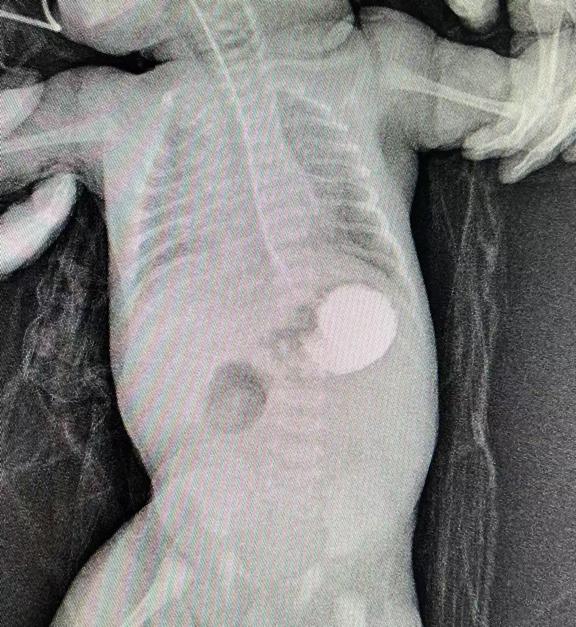

圖片7.jpg

術前造影提示十二指腸遠端閉鎖